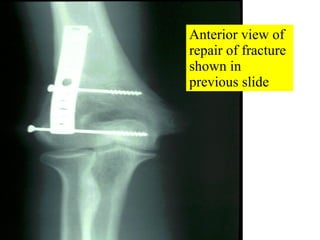

Anterior view of repair of fracture shown in previous slide

Anterior view ofrepair of fracture shown in previous slide